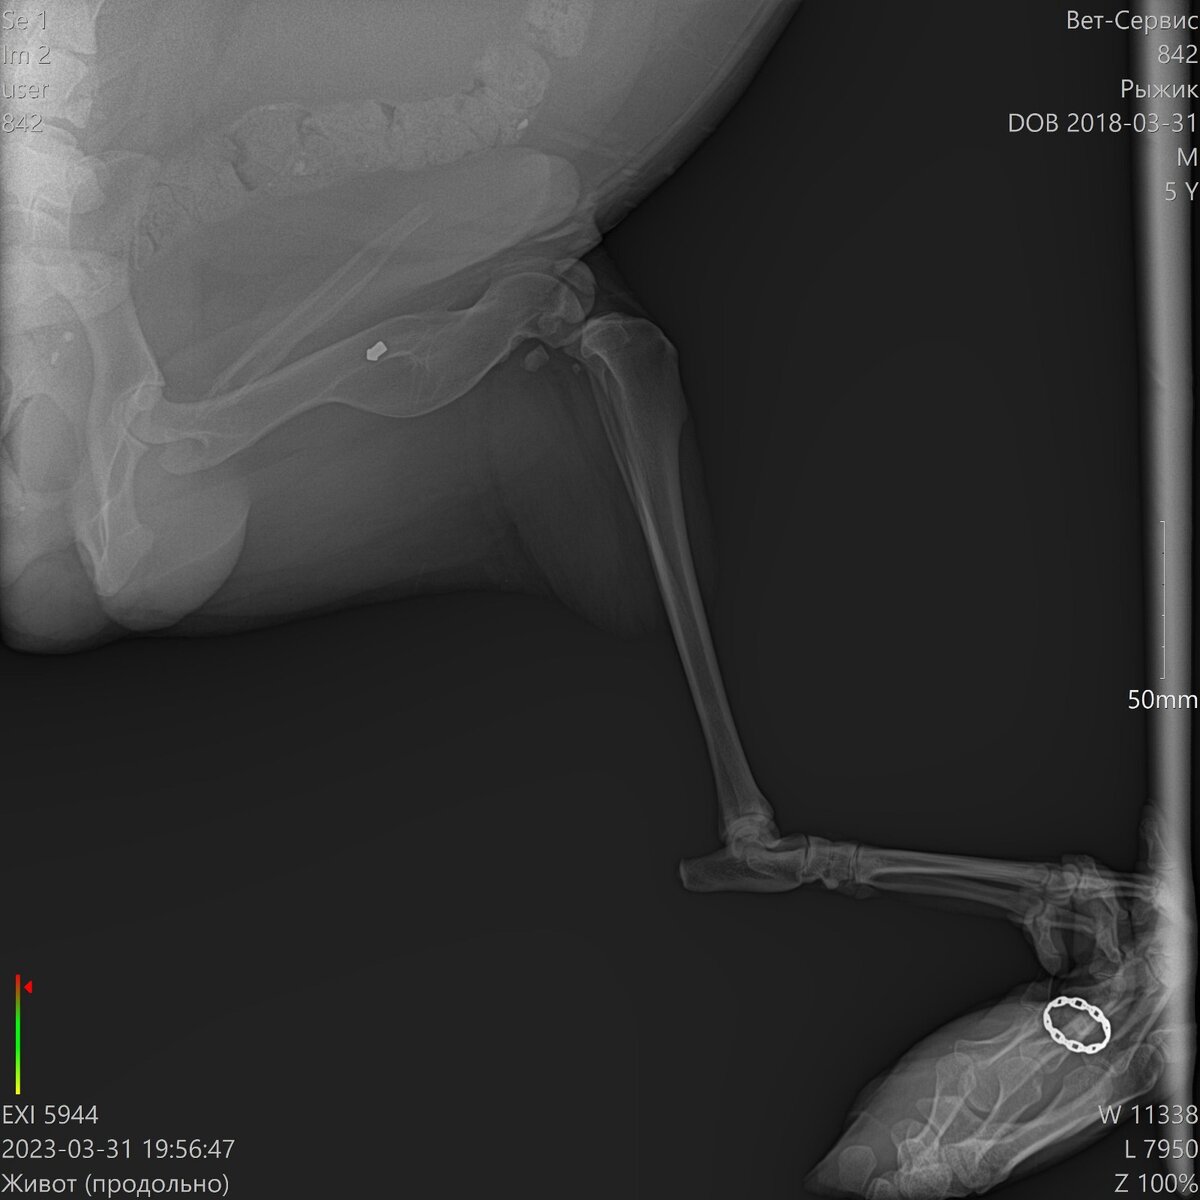

У него перелом позвонка ближе к хвосту ,нужна операция дорогостоящая (15-20 тыс) и мрт (13 тыс примерно)…

Завтра нас уже ждёт хирург с мрт ,тянуть нельзя ,время не наш друг в этой ситуации ((